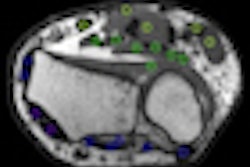

IBA and Wilex recently completed the phase III REDECT trial to determine whether the combination of the radiolabeled antibody Redectane with PET and CT could improve the diagnosis of renal masses, compared with the use of CT alone.

The trial achieved its primary end point, indicating that PET/CT with Redectane correctly diagnosed the presence of clear cell renal cell cancer with a sensitivity of 86% and sensitivity of 87%, findings that reached statistical significance, according to IBA.